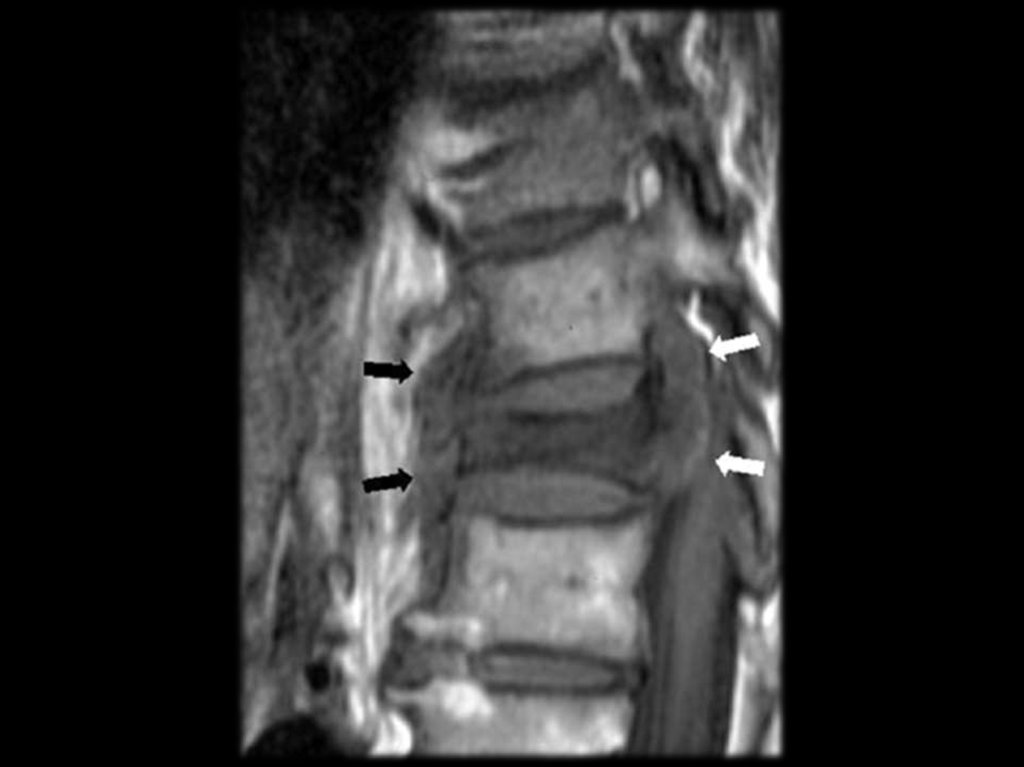

Слева — бруцеллезный спондилит поясничного

отдела позвоночника. Справа — двухсторонний

бруцеллезный сакроилеит.

Поражение позвоночника при хроническом бруцеллёзе